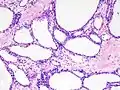

| Micrograph showing a pancreatic serous cystadenoma. H&E stain. | |